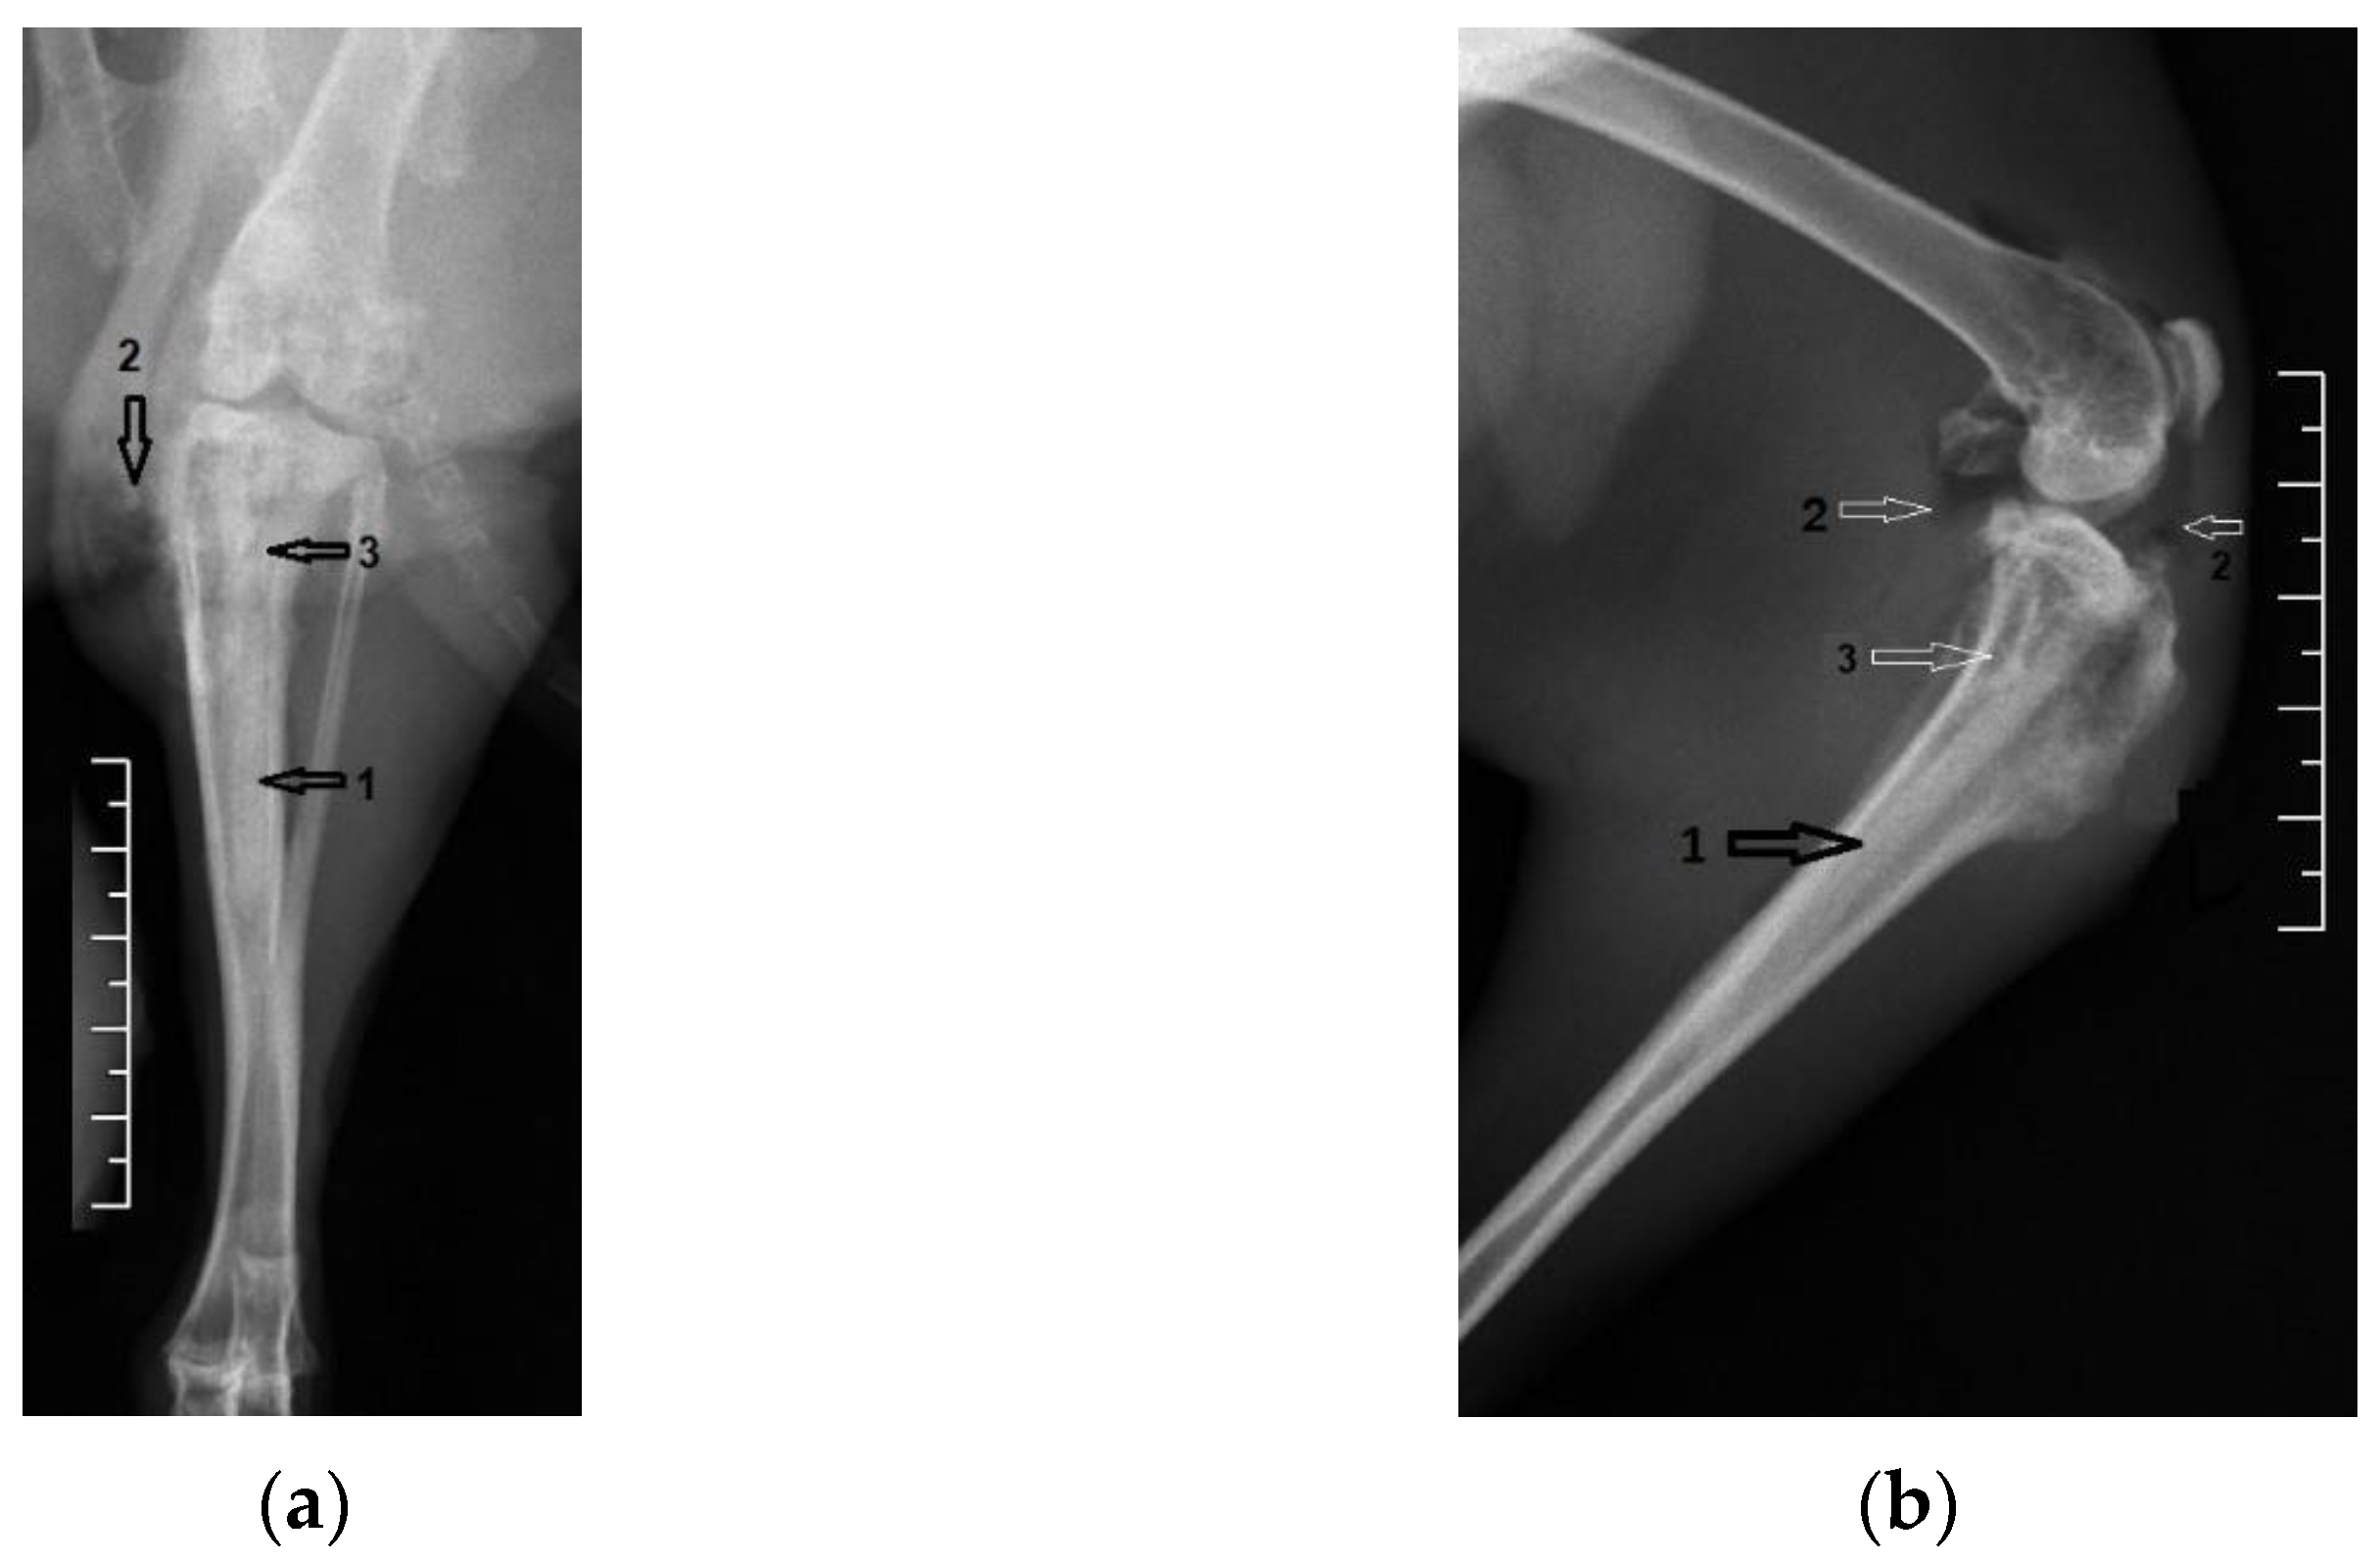

3.1. Radiological Followup